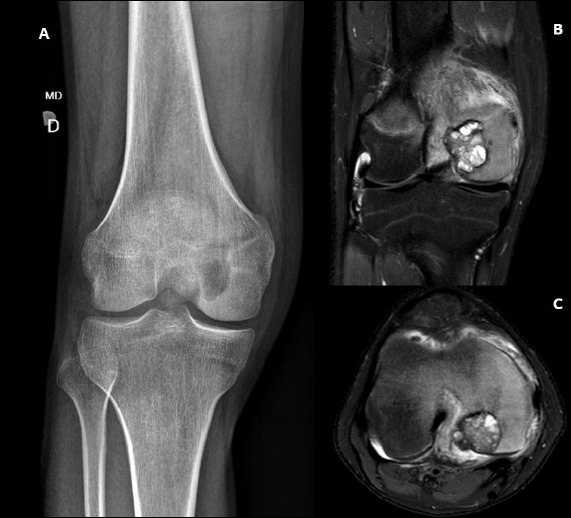

Objective: To describe the clinical and imaging characteristics of chondroblastoma and identify possible factors related to joint complications.

Result: In total, 19 patients were included, 12 (63.2%) of which were mean with a mean age of 13.6±3.5 year. The relation with the local dimension equaled 57.9%, higher in the apophysis of the greater trochanter: 95.2% (p<0.001). Based on imaging, 15.8% patients had an open physis; 55.6%, no damaged physeal line; 42.1%, cortical rupture; 21.1%, secondary aneurysmal bone cyst; 26.7%, violated cartilage; and all cases, medullary edema. 15.8% of cases showed local recurrence and no metastasis. Moreover, 46.7% of patients had relevant secondary osteoarthritis related to the aggressiveness of the tumor according to the Enneking classification (p= 0.041).

Conclusion: The clinical outcome of chondroblastoma show no relation to age, sex, location, physeal status, or presence of calcifications or secondary aneurysmal bone cyst. Progression to secondary osteoarthritis configured the most frequent non-oncological complication and showed a direct relation with the severity of the chondroblastoma. Level of Evidence IV, Case Series.